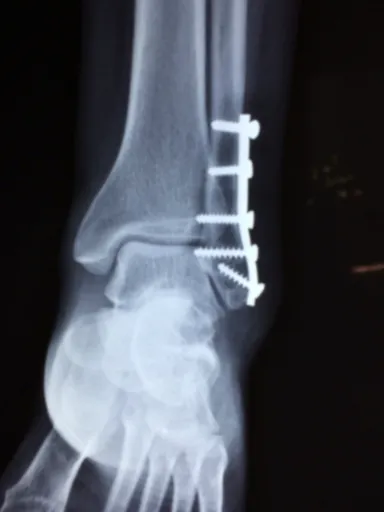

발등 통증의 가장 흔한 원인 중 하나는 부상이나 외상이에요. 스포츠활동을 하거나, 높이가 다른 신발을 착용하면서 발에 무리가 가해질 수 있습니다. 특히, 농구나 달리기 같은 활동에서는 빠른 움직임과 방향전환으로 인해 발등에 부상이 발생할 맛이죠.